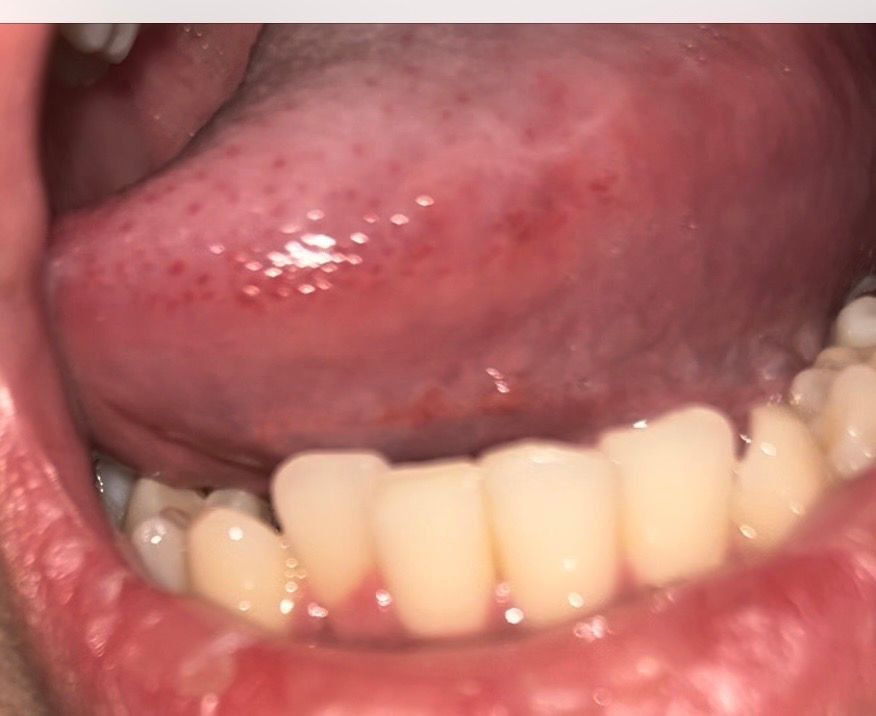

요즘 공부하느라 잠 많이 못 자서 그런지 아니면 깨물었던 건지 구내염이 생겼네요 찾아봤는데 편평태선 이라는 것도 있더라고요 혀 옆면에 붉은 반점 같은게 저렇게 있는데 맞나요? 뭐죠 저게ㅜ 어릴때부터 있었던 거 같아요 또 그냥 구강 상태 괜찮은건가요 20대 초반 흡연자입니다ㅜ 걱정되네요

• 1번 째 사진